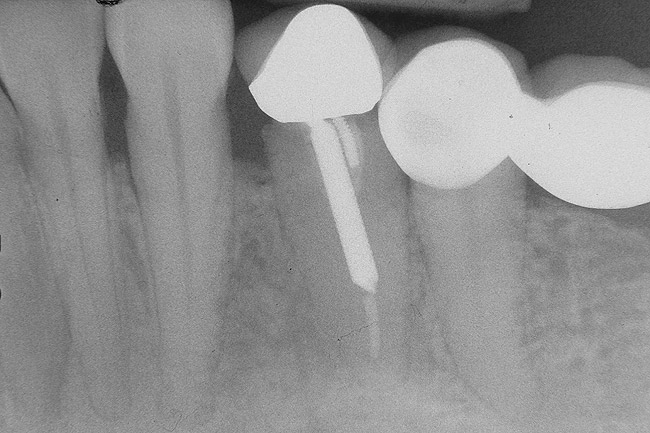

In treatment planning, the decay rate of the patient’s teeth, including the endodontic status of the individual tooth, becomes an important factor when considering long-term outcomes. In the pictured case (Figure 5), tooth No. 11, which previously had been treated endodontically, had recurrent decay and tooth No. 12 had advanced decay with endodontic involvement. In less than 30 days, recurrent decay that reaches the endodontic fill through a leaky restoration (temporary or not), ill-fitting crowns, or broken fillings can re-infect the entire length of the root canal system in a previously endodontically treated tooth.22 Therefore, saving a previously endodontically treated tooth, as in this case, may involve endodontic re-treatment, which can be a deciding factor for tooth preservation.

Figure 5  Recurrent decay of teeth Nos. 11 and 12. Note the proximity of the decay on both teeth to the osseous crest.

Figure 5